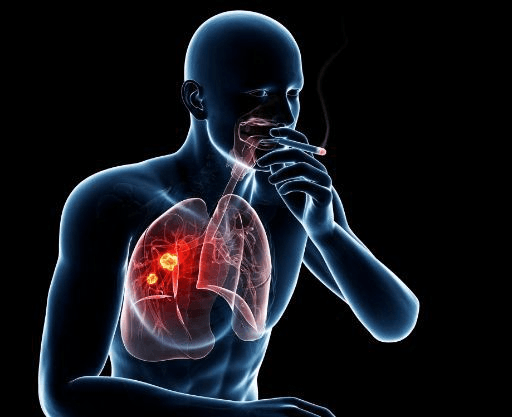

ما علاقة السرطان بالتدخين؟

لا يزال سرطان الرئة يقتل الرجال والنساء أكثر من أي نوع آخر من السرطان، ووفقًا لمنظمة الصحة العالمية فهو في المركز الثاني تبعًا للانتشار على مستوى العالم بعد سرطان الثدي، ولكنه الأول على مستوى التسبب في الوفاة، إذ يموت 9 من كل 10 أشخاص مصابين بسرطان الرئة والذي يعد كل من التدخين والتدخين السلبي السبب الأساسي فيه.

ويرتبط التدخين بالسرطان بشدة أكثر من أي عنصر آخر، فالسموم الموجودة في دخان السجائر تُضعف جهاز المناعة وتجعله أقل مقاومة أمام الخلايا السرطانية أو غير الطبيعية التي تنتشر في الجسم وتنمو بالتالي دون توقف أو رادع.

كما أن دخان التبغ يُتلف أو يغيِّر من طبيعة الحمض النووي وبهذا يُدمر "الدليل" الذي يحدد النمو الطبيعي للخلية ووظيفتها، ومع تدمير هذا الدليل فإن الخلية تخرج عن نطاق السيطرة في النمو وتزيد فرص تشكل كتل سرطانية.

اكتشف الأطباء منذ سنوات علاقة التدخين بزيادة الإصابة بأنواع مختلفة من السرطان، ولا تزال النسب العالمية تؤكد ذلك يوميًا، فتوجد أكثر من 500 مادة كيميائية في السجائر و70 منها يتسبب في السرطان بما لا يدعو إلى الشك، والعشرات منها شديدة الضرر على الجسم كما أكد العلماء على مجموعة مشكلات أخرى يتسبب بها التدخين نتيجة انتشار تلك المواد الكيميائية في الجسم عن طريق الرئة والدم، ومن أهم مخاطر التدخين الأخرى غير السرطان:

حتى إذا لم يؤدي التدخين إلى الإصابة بسرطان الرئة والذي قد يتأثر بنشاط الخلايا، فإن أمراض أخرى مثل الانسداد الرئوي المزمن COPD والتهاب الشعب الهوائية المزمن والسل والسعال المستمر من الحالات الأساسية التي يتعرّض لها المدخنين على مستوى العالم، وتؤدي هذه الأمراض إلى تلف المسالك الهوائية الصغيرة في الرئتين وبالتالي صعوبة كبيرة في وصول الأكسجين لبقية الجسم وتلف الخلايا عموما بمعدل أسرع من المتوقع وبالتالي الإصابة بالأمراض والعدوى أسرع.

وفي النهاية فإن السرطان هو السبب الرئيسي للوفاة على مستوى أنحاء العالم، إذ حصد أرواح أكثر من 10 مليون شخصًا في عام 2020، وإذا كان منه 100 نوعًا ترتبط عادة بالمكان الذي تبدأ منه في الجسم، فإن سرطان الرئة هو الأكثر صعوبة في العلاج وأكثرهم سهولة في الانتشار، وما تتسبب به السجائر من زيادة المواد الكيميائية فإن خطر إصابة المدخنين بسرطان الرئة أكبر بكثير من غيرهم بنسبة من 15-30 مرة أكثر، فضلًا عن الأمراض الأخرى لذا ندعوك الآن لاتخاذ خطوات إيجابية وجادة للامتناع عن هذه العادة على وجه السرعة دون أي تأجيل.